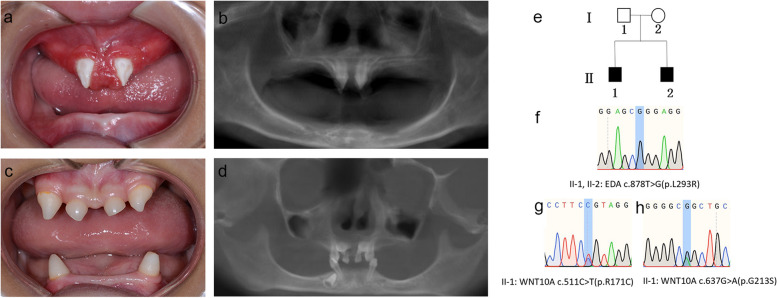

兩名分別為11歲和8歲的親兄弟因先天性牙齒缺失被轉(zhuǎn)診至同佳學(xué)基因具有合作關(guān)系的武漢大學(xué)口腔中心就診。經(jīng)患兒母親及兩名患兒本人簽署知情同意書后,醫(yī)護人員收集了兩位患兒的病史資料,拍攝了相關(guān)臨床照片,并采集了外周靜脈血樣本外送到佳學(xué)基因檢測進行致病基因鑒定基因解碼分析。這對兄弟被診斷為低汗性外胚層發(fā)育不良(HED),均表現(xiàn)出典型的臨床特征,包括少牙(hypodontia)、毛發(fā)稀疏(hypotrichosis)、少汗(hypohidrosis)以及面部發(fā)育異常(facial dysmorphism)。有趣的是,哥哥的牙齒發(fā)育不全明顯比弟弟更為嚴(yán)重。哥哥下頜完全無牙,僅保留上頜兩顆中切牙;而弟弟則仍有部分前牙萌出。

體格檢查顯示,這對兄弟均表現(xiàn)出頭發(fā)稀疏、牙齒缺失及汗腺發(fā)育不良(圖1a-d)。兩人均具有X連鎖低汗性外胚層發(fā)育不良(HED)的典型面容特征:鞍鼻、嘴唇厚大、下頜尖翹以及眼周黑眼圈。

口腔檢查及錐形束CT(CBCT)掃描結(jié)果提示,哥哥(II-1)的所有乳牙及大多數(shù)恒牙均先天缺失,僅保留兩顆錐形上中切牙(#11、21)(圖1a-b)。由于下頜牙列完全缺失,他無法正常咀嚼或建立咬合關(guān)系。

弟弟(II-2)尚保留6顆乳牙(#51、53、61、63、73、83)及3顆恒牙胚(#11、21、43)(圖1c-d)。

Fig. 1

圖1:HED兄弟患者的牙齒特征與面部表現(xiàn)

a-b:**兄長(II-1)**的口腔狀況及全景X線片。

c-d:弟弟(II-2)的口腔狀況及全景X線片。

e:家系圖,黑色方塊代表HED患者。

f:DNA測序圖譜顯示兩位兄弟(II-1,II-2)攜帶

EDA基因雜合變異c.878T>G(p.L293R)

。

g-h:兄長(II-1)同時攜帶兩個WNT10A基因雜合變異:c.511C>T(p.R171C)和 c.637G>A(p.G213S)。

在兩兄弟中均檢測到EDA基因c.878T>G(p.L293R)的錯義變異,但復(fù)合雜合型WNT10A基因變異(c.511C>T(p.R171C)和c.637G>A(p.G213S))僅在兄長中發(fā)現(xiàn)。

母親臨床表型正常,未出現(xiàn)毛發(fā)、汗腺或牙齒相關(guān)異常。WES檢測顯示其為EDA基因c.878T>G雜合變異及WNT10A基因c.511C>T雜合變異的攜帶者。上述結(jié)果均經(jīng)Sanger測序驗證(圖1e-h)。